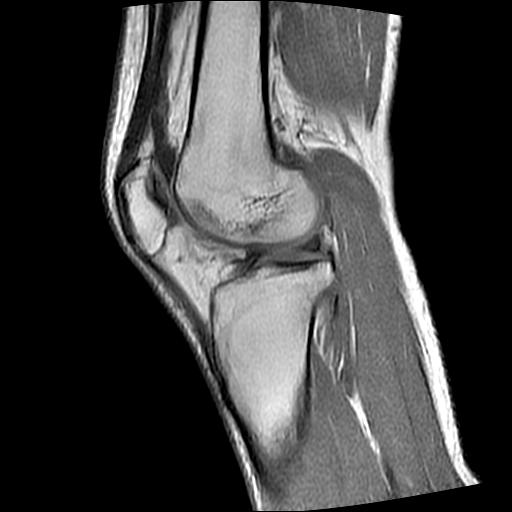

40岁男性,右膝关节外伤,x光平片示,髁间隆突撕脱骨折。

1、前交叉韧带撕裂;

2、外侧半月板后角撕裂;

3、关节腔积液。

前交叉韧带撕裂,关节腔积液.

半月板1-2级损伤   前交叉韧带撕裂伤   关节腔少量积液  诸骨未见新鲜外伤性改变

髁间隆突撕脱骨折;内侧副韧带损伤。

内侧副韧带撕裂及关节腔积液是肯定的,但是前交叉撕裂确定吗?会不会有容积效应的因素,因为前一张前交叉显示清楚,连续性良好,且较光滑。请问楼主有关节镜支持吗?我们医院也经常有这样的患者,但苦于没有关节镜,而无法对照、证实(除非完全断裂),出现了不同的诊断结果只能毫无意义的争论。

1、前交叉韧、内侧副韧带撕裂;

3、关节腔积液。4、髁间脊撕脱骨折。